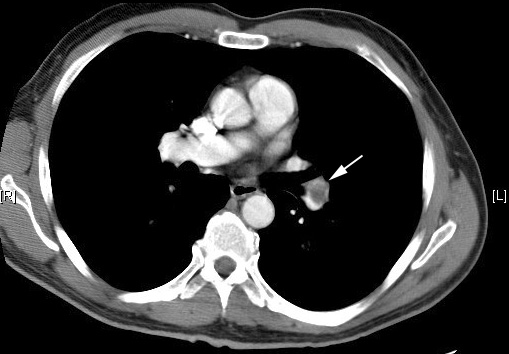

Pulmonary Embolus

Arrow: Filling defect in pulmonary artery. |